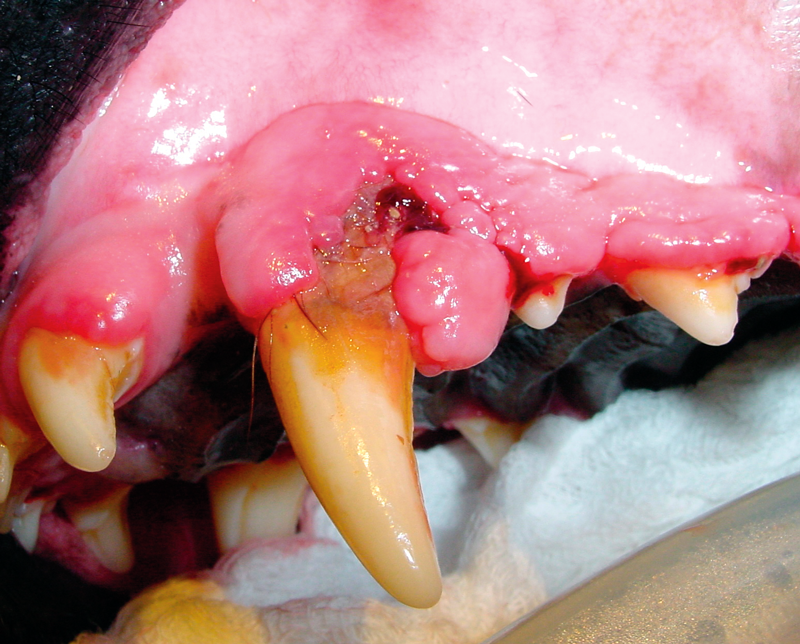

The image depicts gingival hyperplasia in a dog. In the case of hyperplasia, the tissue/organ is enlarged due to:

Increased number of the cells